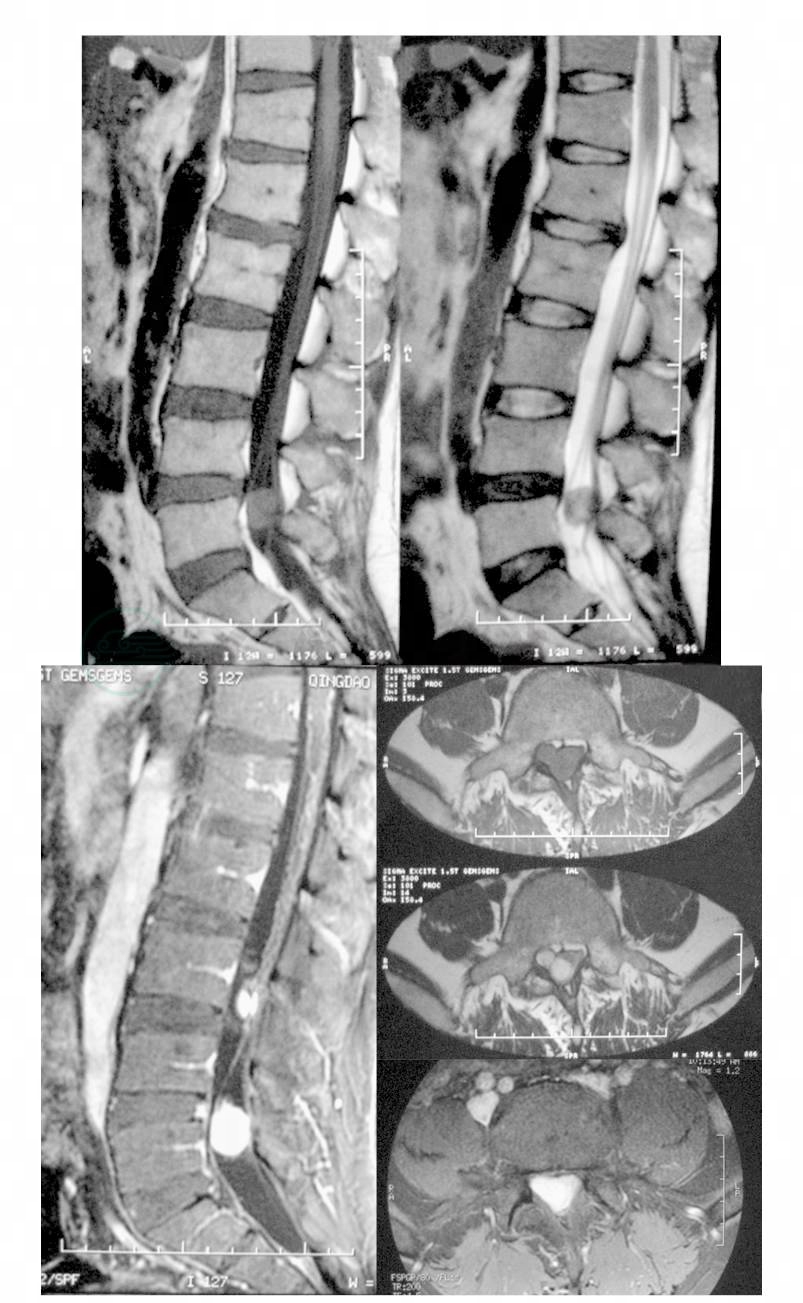

男性,37岁,因“腰痛伴双下肢麻木1年”而入院。患者2006年4月因腰背痛在外院就诊,行腰椎MRI检查,发现L5椎管内硬膜下类圆形占位性病变,等T1混杂T2信号,均匀明显强化(图1)。行手术切除,病理报告为血管周围瘤。术后患者症状完全消失。术后半年,患者再次出现腰痛伴右下肢疼痛麻木,活动后症状加重,休息后不能完全缓解,来我院就诊。查体:腰椎屈伸活动无明显受限,右小腿前外侧及足背皮肤痛觉减退,右𧿹背伸肌力Ⅲ级,双侧膝反射(+ + ),踝反射(+ + ),右侧直腿抬高试验45°(+ )。复查MRI:见L5椎体后方又出现一类圆形等T1混杂T2信号占位性病变,部位、形状和信号特点均与前一次MRI所见相似(图2)。初步诊断为腰椎管内肿瘤术后复发。在我院行第二次手术,经原切口进入,分离保护好右侧L5和S1神经根,将肿瘤连同周围部分硬膜和瘢痕组织一并切除。病理报告为:腰椎管内血管周细胞瘤,免疫组化:EMA(-),NF(-),Vimentin(+ )(图3)。术后患者症状明显减轻,术后半年复查腰椎MRI:未见肿瘤复发征象。

图1 L5椎管内硬膜下等T1混杂T2信号占位性病变,强化均匀、明显

图2 L5椎体后方占位性病变,部位、形状和信号特点与图6-4-10相似